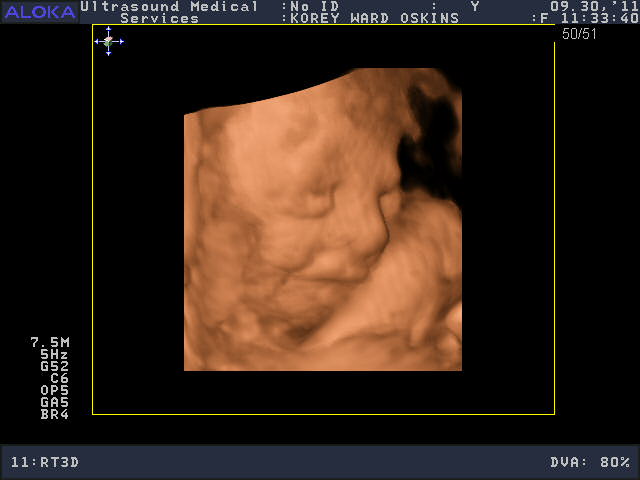

He was a very stubborn baby, so it was really kind of nerve-wracking at first thinking we might not get a single good picture. His face was squished up against the placenta and he wouldn’t budge. You’ll see that in the pictures below; it looks like an enveloping cloud or a scallop shell. Finally he moved a bit and we got some glimpses of his face. We saw him make some facial expressions, wiggle his fingers, and move his mouth around. We were curious to see whose nose he would have, and in some pictures, it looks like he has Josh’s, in others, mine.

So who do you think he looks like?

He is sooooo cute! Personally, I think he looks like ME.